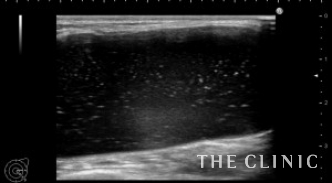

本日は横浜院でヒアルロン酸のしこり除去を行いました。

4年前にヒアルロン酸豊胸をしましたが、両側の乳房に8cm大のしこりになったため相談に来られました。

しこりになったヒアルロン酸です。

ヒアルロン酸注入によるしこりのエコー診断カルテ